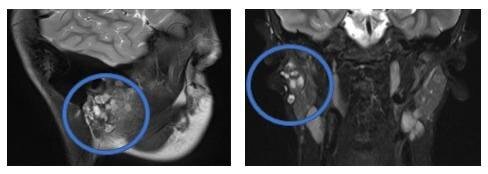

10-сантиметровую опухоль слюнной железы удалили 12-летнему мальчику врачи Центра Рошаля.

Двухчасовая операция была сложной из-за того, что ребёнку уже производили подобное вмешательство раньше. На этом же месте образовались новые опухолевые узлы.

«Главная сложность заключалась в том, чтобы аккуратно выделить и отделить ветви лицевого нерва, проходящие через эту область», — рассказал челюстно-лицевой хирург.

После операции у мальчика сохранились все двигательные функции лица, и его выписали из больницы.